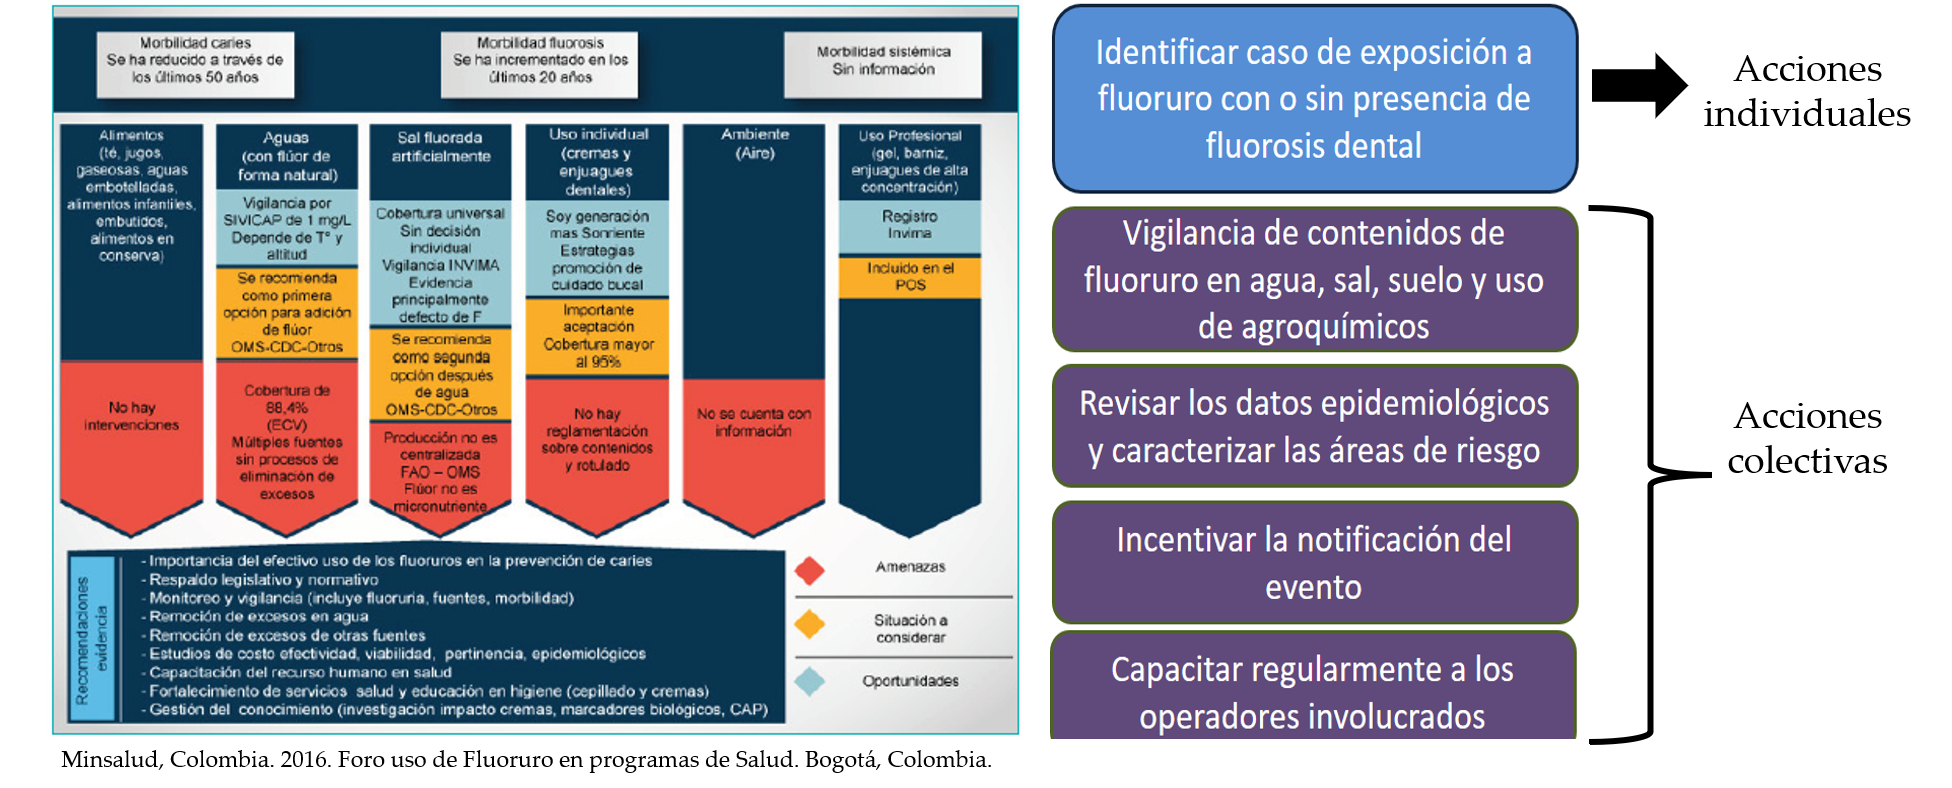

Mecanismos para la vigilancia epidemiológica de la Fluorosis